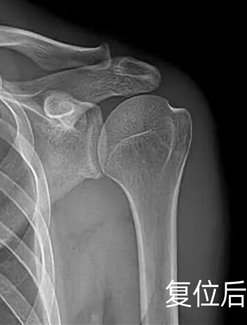

医生会根据脱位情况选择合适的复位手法(如足蹬法、牵引回旋法),整个过程速度很快,复位成功后会听到“咯噔”一声,疼痛会立即缓解,肩膀可初步活动。